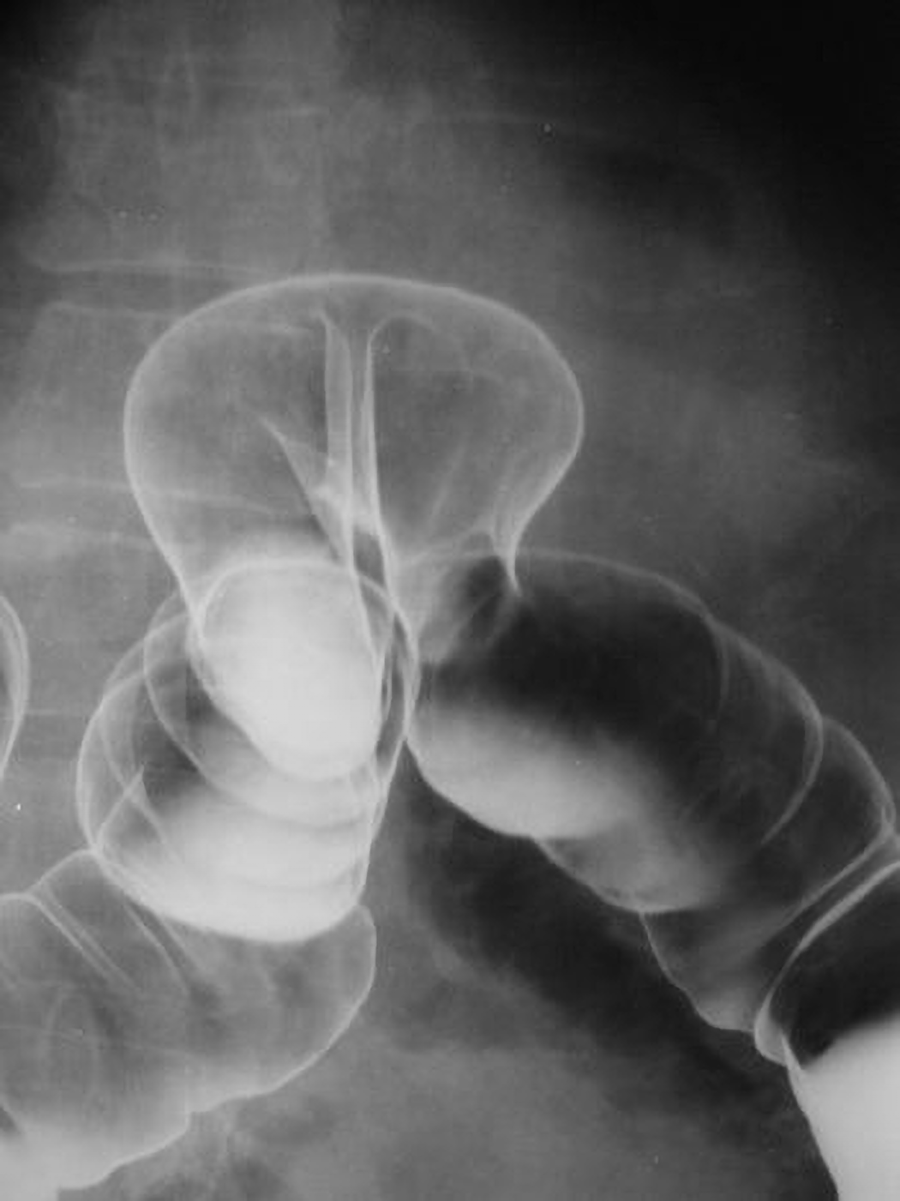

Another diagnostic procedure that uses barium is a barium enema, which is a diagnostic procedure involving the use of a contrast material known as barium. Barium coats the inner wall of the large intestine for visualization. During the procedure, barium is administered into the rectum, along with air (which appears black on X-ray). Fluoroscopy is often used during a barium enema. During fluoroscopy, a continuous X-ray is passed through the large intestine and is transmitted to a monitor so the movement of the barium through the large intestine can be visualized as it is instilled through the rectum. After the procedure, if the barium isn’t completely eliminated from the body, constipation or fecal impaction may occur.

The image below shows a barium enema showing herniation of the colon. The colon bends upward and back down at the site of the herniation. The barium causes the colon to appear white on the left side of the image, on one side of the herniation, and air in the colon causes it to appear black on the right side of the image, on the other side of the herniation.

Herniation shown on a barium enema of the colon.